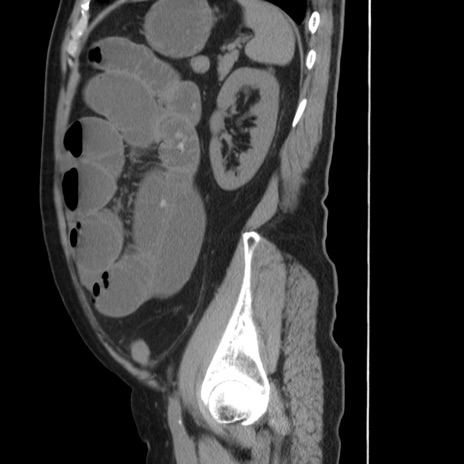

症例20(矢状断像)

【症例】 60歳代男性

【主訴】 腹部膨満、嘔吐

【現病歴】5日前頃より倦怠感を認め食事量減少し4日前の朝嘔吐、食事摂取困難となった。 3日前近医受診し点滴施行され整腸剤などを処方された。 当日他院を受診し、腹部膨満著明、炎症反応の上昇(CRP10.8、WBC11200)あり、紹介受診となる。

【身体所見】 意識JCS1 受け答えがはっきりしないBP 111/57mHg、 P 67bpm、、BT35.2°C、SpO2 97%(RA)、 腹部:膨隆、打診で鼓音あり、全体的に圧痛有り、腸蠕動音(-)、反跳痛ははっきりせず。

【データ】WBC 11400、CRP 14.20